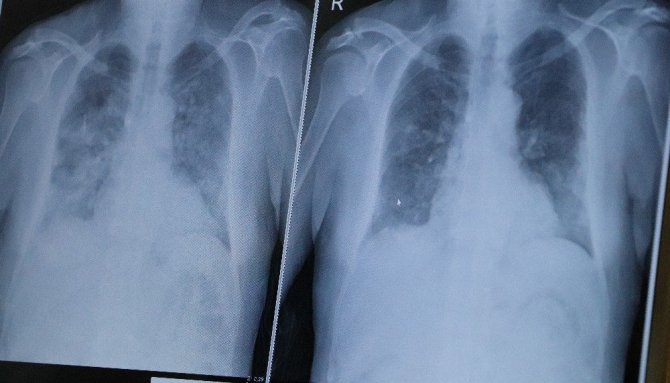

Samsun'un toplum dinamiklerine uyamadığını söyleyen Prof. Dr. Özkaya, "Kontrollü hayatımıza devam edemedik. 2 Şubat'ta vaka sayımızı çok aza düşürmüşken maalesef 2 Mart'ta yüz kızartıcı kırmızılığımızın arttığını görüyorsunuz. Önümüzdeki günler çok önemli çünkü eğer bu kırmızılığı normale getiremezsek, sadece hastanelere dolan vakalarla uğraşmak zorunda kalmayız aynı zamanda çok katı yasaklar da gelebilir. Belki günlerce, haftalarca tamamen kapanabiliriz. Sokağa çıkma yasağı tekrar ilan edilebilir, günlerce bu sürebilir. Eğer "biz yasakları önemsemiyoruz, bizim için önemli değil" diyorsanız bir kötü basamak daha var. Gerçekten mutant virüsler herkesi etkiliyor. Bunun mutant olduğu kanıtlanmış, ülkemizde ve Karadeniz'de de. Sadece yasaklarla uğraşmak değil, sevdikleriniz kaybetmek zorunda da kalabilirsiniz. Kovid-19 pozitif olarak tedavi altındaki 70 yaşında bir hastamız 1 günde kötüleşti ve neredeyse kendisini kaybediyorduk. Eğer bu hastamız evde olsaydı, kaybetmiştik. Vaka sayısının azaltmak elimizde, bunun 2 yolu var: İlk olarak aşıdır. İkincisi ise kontrollü yaşama, maske, mesafe, hijyene dikkat etmektir" ifadelerini kullandı.